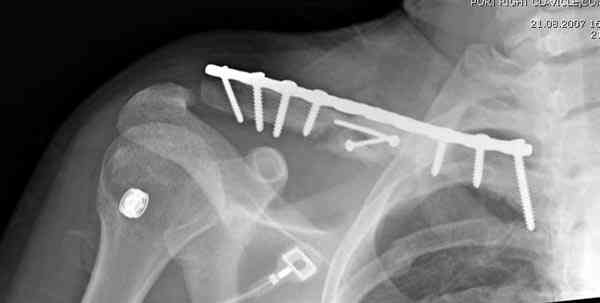

Второй случай тоже недавно оперирован по поводу

ложного сустава, в марте травма, через 4.5 половиной

операция..